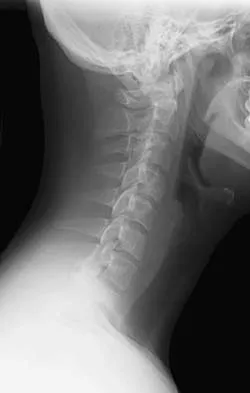

Master AAOS & ABOS exams with Set 4 practice MCQs on high-yield spine surgery. Covers vertebral fractures, ce…

Master AAOS & ABOS boards with Spine Surgery MCQs (Set 3). Practice questions cover degenerative spine diseas…

Prepare for your AAOS & ABOS Spine Surgery exams with Set 2 of high-yield MCQs. Cover essential topics like s…